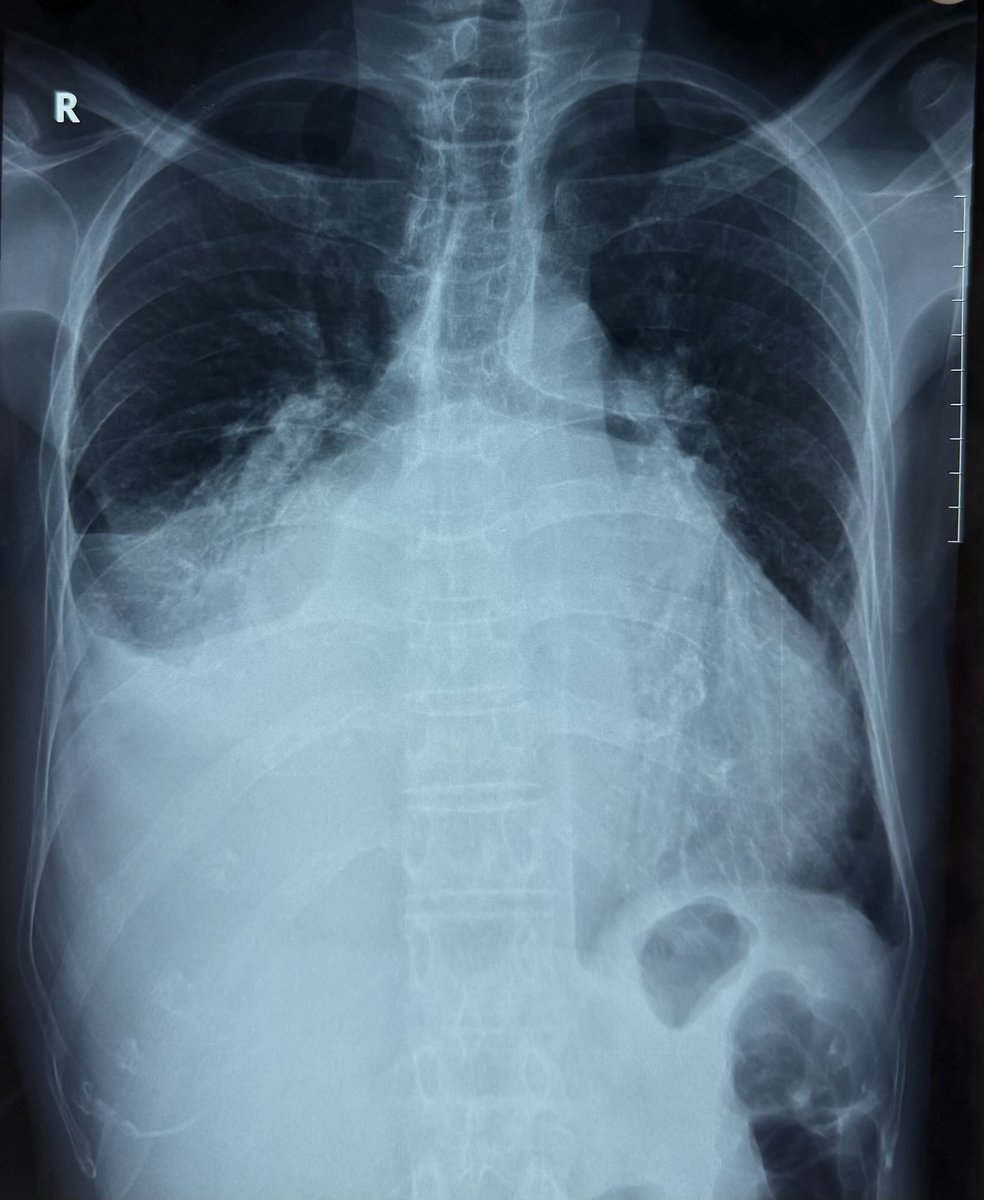

“Splaying of carina” or “flattening of Carina”? Terminal phases of RHD!! There are people not willing to get operated, go on suffering and thus teaching us the natural history of diseases many of which are available only in text books. Qn to fellows, what is normal carinal angle?